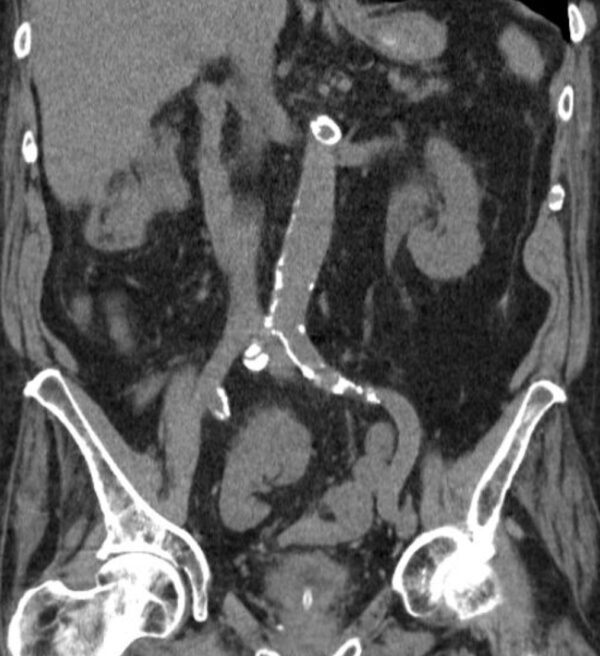

Case 49

https://radiopaedia.org/cases/pelvic-kidney-1

Modality

CT

Region

GUT